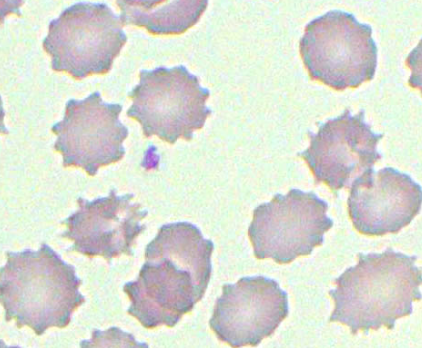

Pyruvate Kinase Deficiency

Results in the formation of echinocytes due to decreased ATP

Burr Cells

Other term for echinocytes; due to an accumulation of lipids in the outer half of the red blood cell's membrane